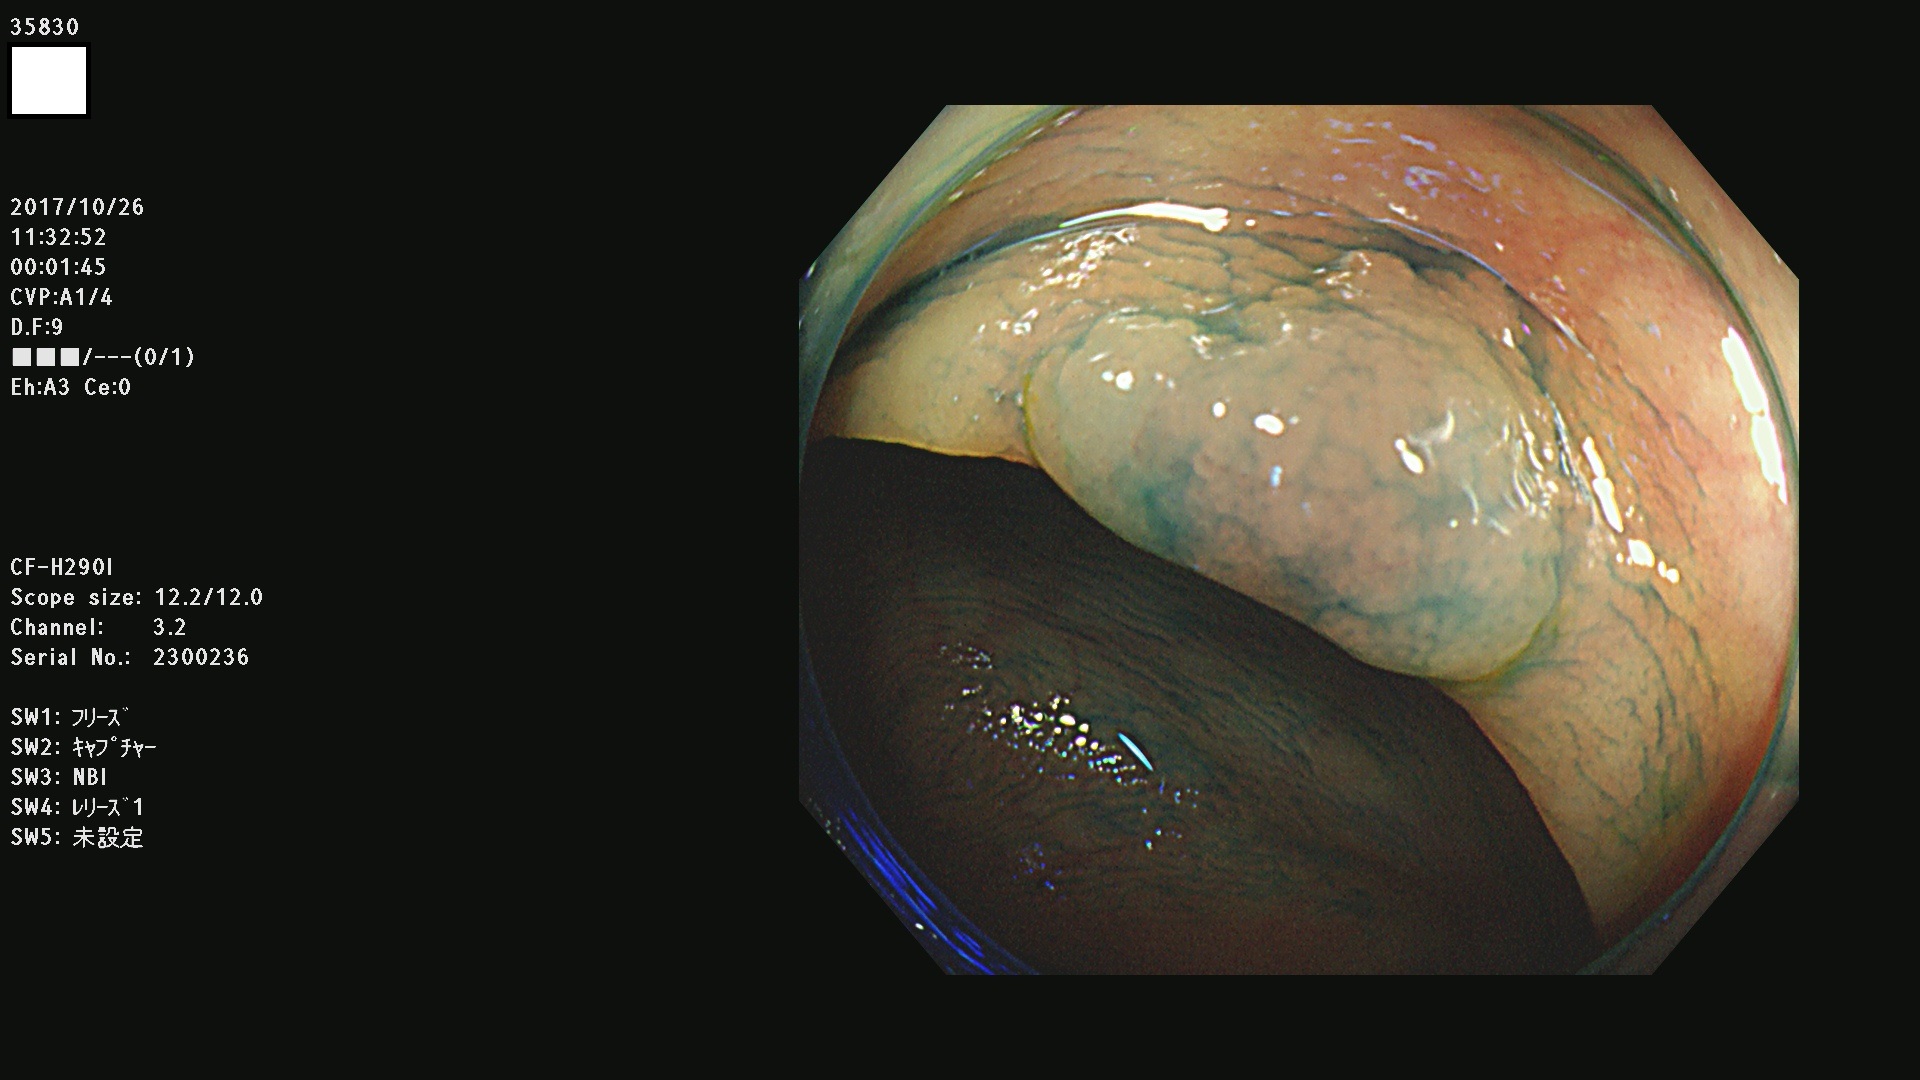

35801 35802 35806 35808 35816 35820 35821 35826 35828 35830(SSA/Pのみ) 35833 35834 35835 35837 35838 35840 35841 35843 35847 35852 35855 35857 35859 35863 35864 35865 35866 35867 35869(SSA/Pのみ) 35872 35873 35875 35878 35880 35882 35885 35886 35888 35890 35893 35895 35896 35897 35898

発見困難で危険性の高い平坦型病変(上記100名より抽出)